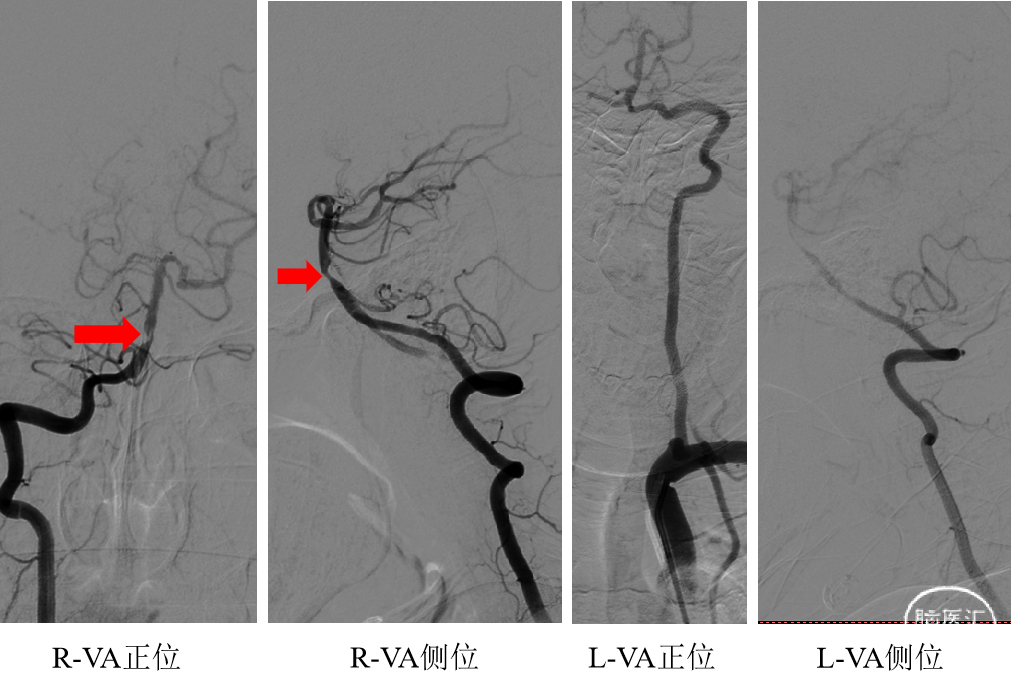

造影结果:

左侧颈内动脉起始段重度狭窄

晚期可见左侧颈内动脉通过后交通向基底动脉代偿供血

右侧椎动脉开口重度狭窄

基底动脉闭塞

病例特点分析:

桥脑外侧(右侧小脑桥臂)梗死

左侧颈内动脉重度狭窄

基底动脉显影欠佳

该患者右侧椎动脉开口位置偏高,相比股动脉入路,经桡动脉入路,导丝更易超选入右侧椎动脉。

该患者基底动脉闭塞,左侧颈内动脉造影显影晚期向基底动脉代偿供血,因此行左侧起始段支架植入可增加向基底动脉的代偿供血。